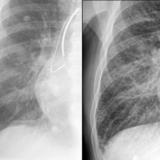

APE 1

Date: 11/05/2005

Views: 4072

APE 2

Views: 2684